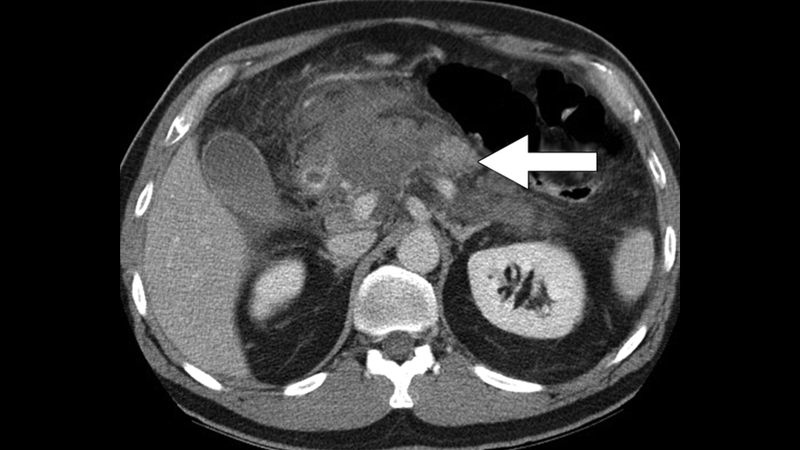

Dưới đây là hình ảnh viêm tụy cấp có biến chứng hoại tử trên CT của một người đàn ông 45 tuổi. Trên hình ảnh CT, phần lớn tuyến tụy không tăng sáng ngoại trừ một phần nhỏ thân tụy (mũi tên). Bệnh nhân này có nguy cơ bị ngắt kết nối ống tụy vì mô tụy sống bị tách khỏi đường tiêu hóa bởi mô hoại tử.

Hình ảnh viêm tụy cấp có biến chứng hoại tử trên CT của một người đàn ông 45 tuổi